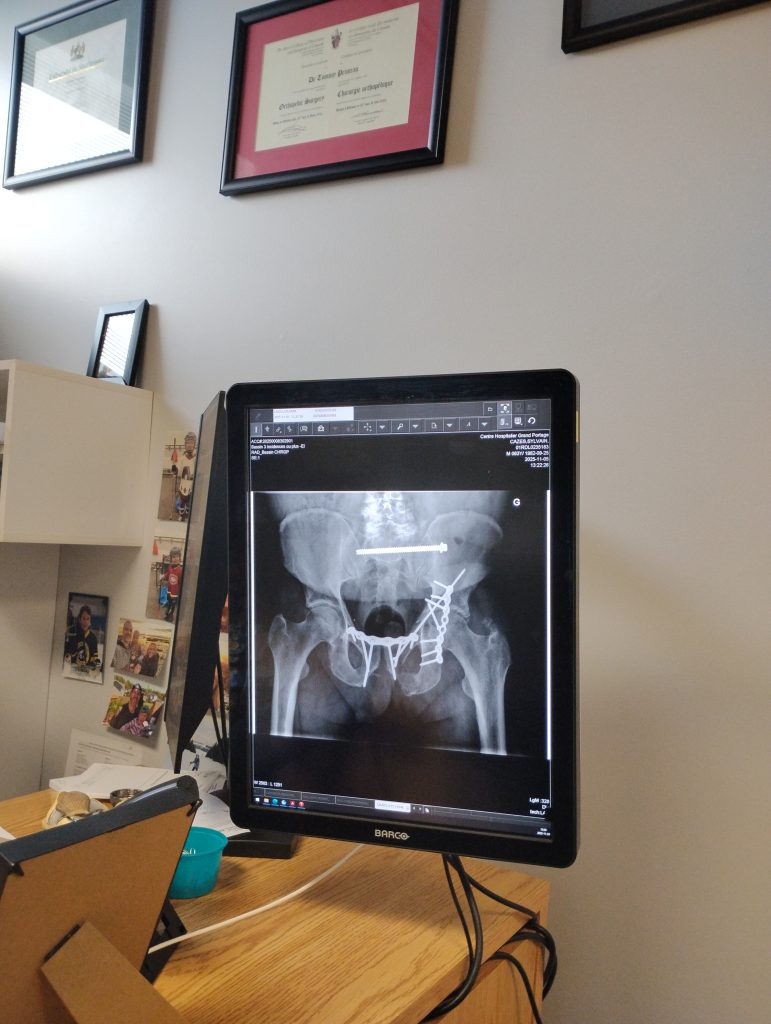

L’opération dure cinq heures. Il sort de là sans vraiment savoir ce qu’ils ont fait. Il n’a pas posé de questions. Il était dans un autre monde. Mais la réponse, il la résume en une phrase qui revient souvent. « Ils m’ont mis des vis partout. Je suis tout vissé », dit-il, montrant une photographie d’une radiographie qui ne laisse aucune place à l’interprétation. « L’arrière de mes hanches ne bouge plus comme avant. Là où il y avait des ligaments, tout est maintenant fixé. »

En réadaptation, son moral descend. « La nourriture n’était pas mangeable. J’ai perdu 27 livres. » Il finit par imposer son menu de survie : soupe, yogourt, jello, café. Puis, il peut enfin rentrer chez lui avec un suivi tous les deux mois. « J’ai dû attendre douze semaines pour la consolidation avant de mettre du poids. Lorsque j’ai pu me lever, j’ai demandé à voir mes radiographies pour comprendre ce qu’on m’avait fait. » Il est frappé. « Quand je montre ces images aux gens, ils me demandent comment je fais pour être encore debout ».

Cette radiographie parle d’elle-même. Photos : Marc Larouche